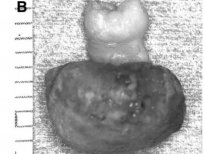

Diş yapısı en dıştan içe doğru mine (kök kısmında sement), dentin, pulpa olarak sıralayabiliriz. Mine, sement ve dentin hidroksiapatit kristalleri dediğimiz kalsifiye yapıdan oluşur ve büyük ölçüde kemiğe benzer. Hidroksiapatit kristalleri dişlere sertliğini verir ve dişlerin molekül yapısında eser miktarda su bulunduğundan dolayı oldukça serttir ve böylece çok büyük çiğneme kuvvetlerine dayanabilirler. Mine, vücuttaki en sert maddedir; öyle ki kemikten bile daha serttir. Bu kadar yoğun kalsifiye yapıların yumuşak dokuda gelişmeleri oldukça zor ve nadir olmasına rağmen çarpıcı örnekleri vardır.